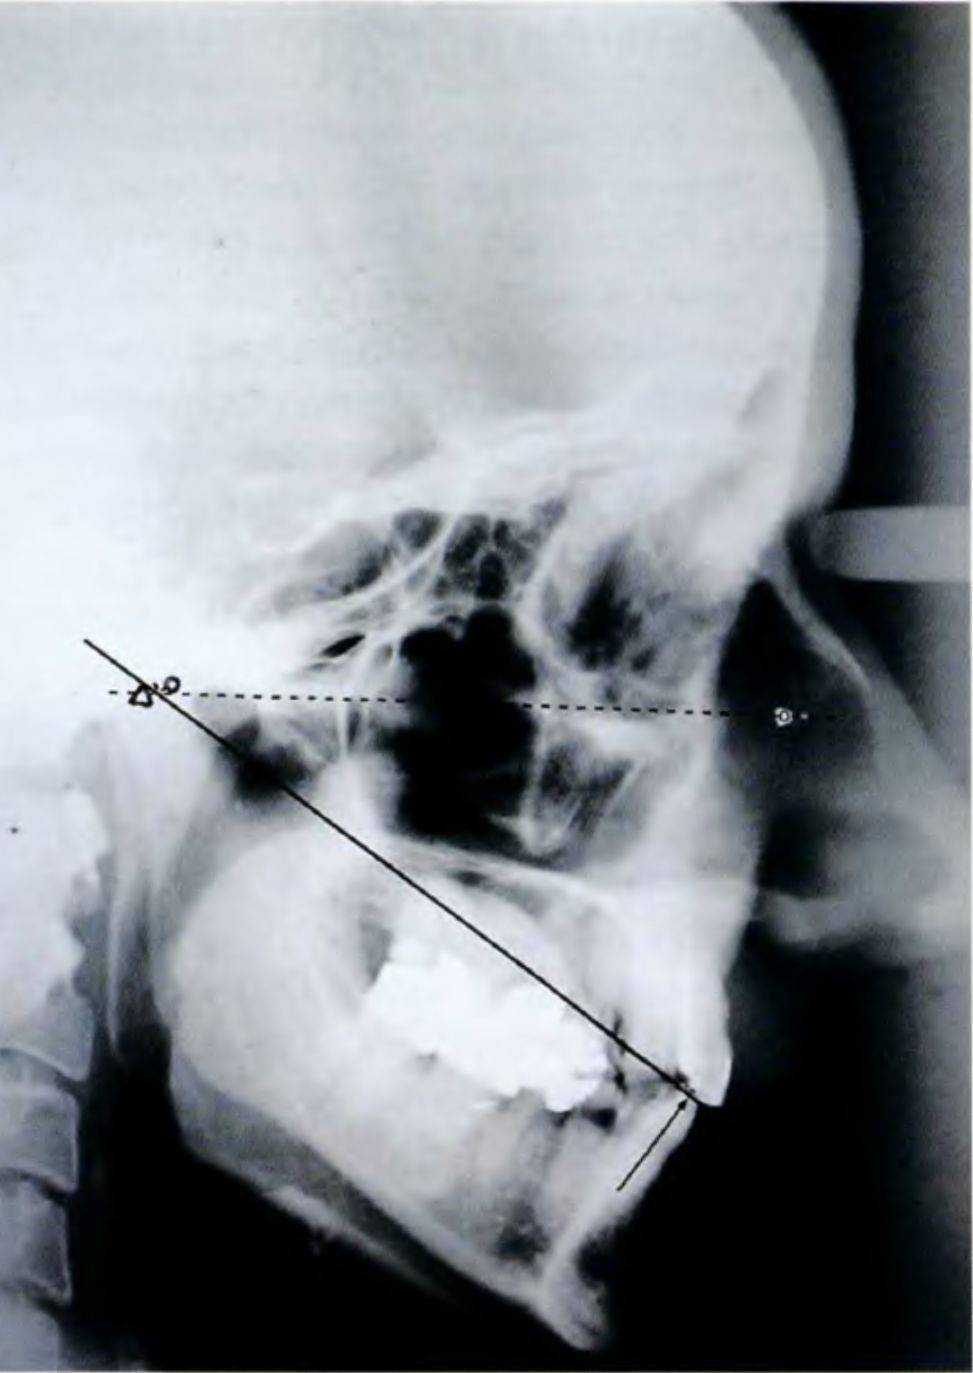

Рис. 6-Бд. Функциональный анализ цефалограммы

Боковую цефалограмму для функционального анализа получают при расположении челюстей в центральном соотношении (рис. 6-5д). В данном случае угол СП-ОГП составил 31°. Таким образом, окклюзию можно увеличить так, чтобы угол СП-ОГП увеличился на 1°.

Для передачи этого показателя в артикулятор сопряженную плоскость нарисовали так, чтобы угол

СП-ОГП составил 32° (рис. 6-5h). После этого измерили расстояние между двумя линиями на уровне режущего края нижнего переднего зуба, которое составило 2,5 мм.

Как можно увидеть в области основания носа, увеличение изображения на боковой цефалограмме составляет 1:1,10. Данную шкалу использовали для определеня степени увеличения окклюзии, с учетом чего откорректировали разделитель (4 мм). Таким образом, полученное значение перенесли в артикулятор и откорректировали резцовый штифт.